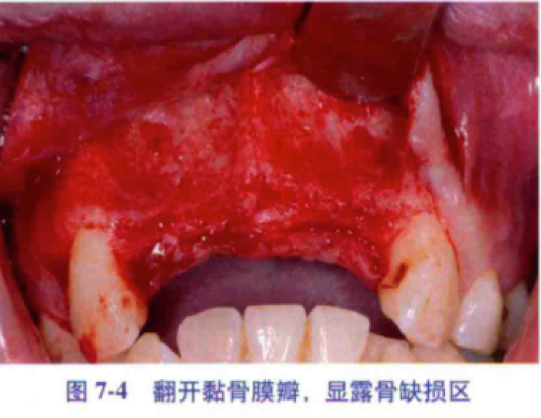

2、翻瓣

粘骨膜瓣的剥离及翻起过程中应注意保持其完整性,尽量在骨膜下剥离。上颌前牙区,往上需剥离到梨状口的下缘,露出部分鼻粘膜,在植骨后伤口关闭前做软组织松弛处理时,应避开此黏膜以免切透后导致植骨区与鼻腔相通。但在剥离至前鼻棘时,其上的软组织可不完全剥离,以免术后患者鼻翼变宽或鼻中线偏移。